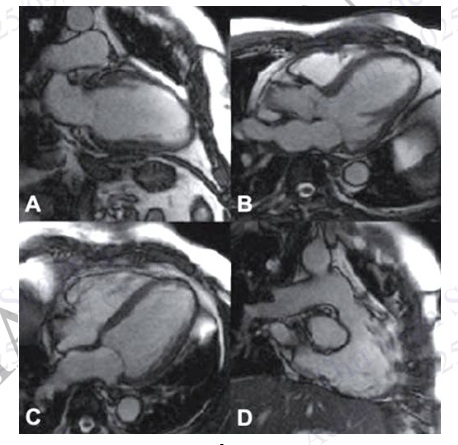

Hình 4.88. Mặt cắt chuẩn trên cộng hưởng từ tim